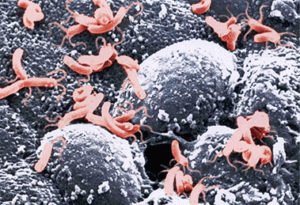

Helicobacter

Ennek fő oka gastroduodenita - mikroba Helicobacter. Ő gyorsan alkalmazkodott az antibiotikumokra. Folk jogorvoslati ne vigyen.

Hogyan működik a Helicobacter

A gyomor egy karbamid, átható, hogy a váladék a kapillárisok. Helicobacter speciális enzim-molekula bomlani kezd ammóniára és szén-dioxid, zaschelachivaya közegben. Ez lehetővé teszi, hogy a fertőzés, hogy rendezze a falakon. Gyulladás fejlődik.

A Helicobacter pylori baktérium

Megfertőzni elég egy puszit. A baktériumok bejutását a szervezetbe szájon keresztül.